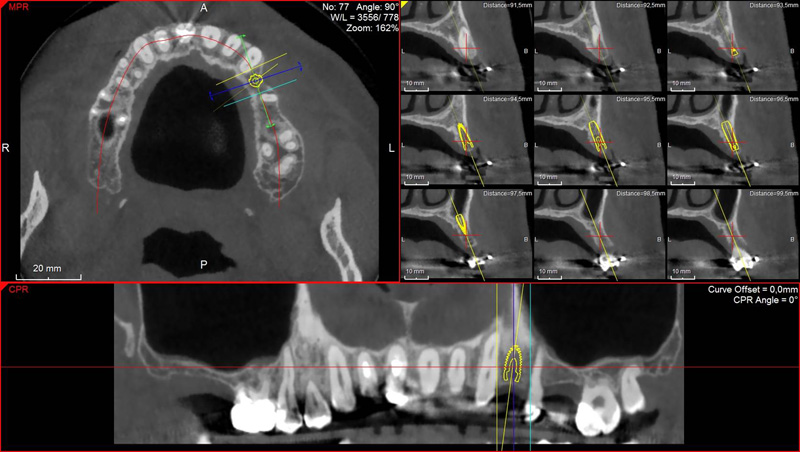

coDiagnostiX – Dental Wings

Jedná se o externí plánovací program, spojený se zubní laboratoří a frézovacím centrem, který využívá dat získaných z 3D rentgenu čelisti, otisku zubů a dásně (scanu zubů a dásně) a finálního návrhu protetické náhrady.

Tento program umožňuje tříprostorovou počítačovou simulaci při plánování pozic implantátů. Součástí programu je i databáze, ve které mohou být uloženy všechny typy implantátů od všech výrobců, včetně jejich délek, průměrů i tvarů.

Lékař si vytvoří všechny typy zobrazení potřebných pro naplánování – tedy 2D snímky (panoramatický), příčné řezy i 3D model.

Vidí zde i důležité anatomické útvary – čelistní dutinu, průběh nervu atd. Po proměření množství kosti – šířky i výšky vybere z databáze vhodný typ implantátu a umístí ho do požadované lokality. Ihned vidí jeho pozici ve všech 3 rovinách a na

všech snímcích i 3D modelu. Může upravovat podle potřeby jeho pozici, sklon atd.

Všechny vybrané a správně umístěné simulované implantáty se ukládají do „počítačové karty“ pacienta s jejich pozicí, délkou, průměrem, typem i sklonem. V programu také lékař navrhuje chirurgické šablony pro řízenou nebo navigovanou implantaci.

Lékař i pacient tedy ještě před vlastní operací vidí, jak by mělo ošetření probíhat a vypadat.